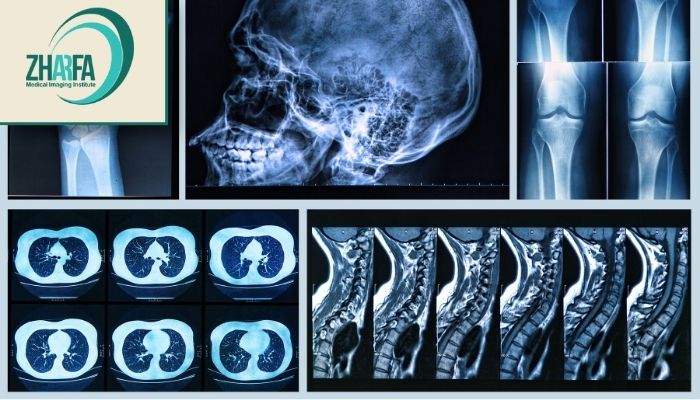

خدمات رادیوگرافی مرکز دکتر حیدری: تشخیص دقیق و سریع بیماریها

رادیوگرافی یا پرتونگاری یکی از روشهای اصلی و پرکاربرد در تصویربرداری پزشکی است که در آن از تابش اشعه ایکس برای تولید تصاویر از داخل بدن استفاده میشود. این اشعه قادر است از بافتهای نرم مانند پوست و عضلات عبور کند در حالی که بافتهای سخت مانند استخوانها مانع عبور آن میشوند و در نتیجه در تصاویر به رنگ سفید ظاهر میگردند. این تکنیک به پزشکان کمک میکند تا بهطور دقیقتری بیماریها، آسیبها و اختلالات موجود در بدن را تشخیص دهند.

استفاده از تجهیزات پیشرفته تصویربرداری

در مرکز ژرفا از تکنولوژیهای نوین و پیشرفته مانند رادیوگرافی دیجیتال و سونوگرافی استفاده میشود که امکان تشخیص دقیق و زودهنگام بیماریها را فراهم میآورد. این تجهیزات پیشرفته بهویژه برای شناسایی بیماریها در مراحل اولیه و تودههای کوچک بسیار مؤثر هستند و به پزشکان کمک میکنند تا تصاویر واضح و دقیق از ساختارهای داخلی بدن دریافت کنند.